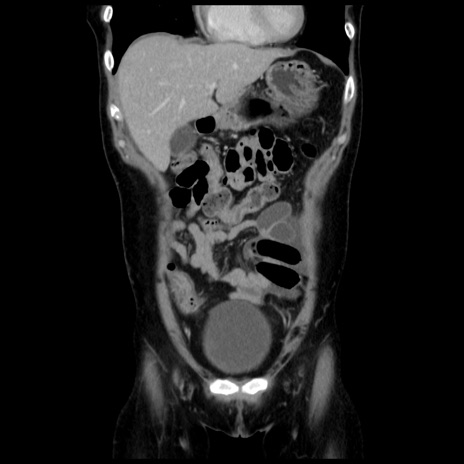

症例10(冠状断像)

【症例】 50歳代女性

【主訴】 腹痛

【現病歴】前日生レバーを食べた。今朝に排便あり。 昼前に突然発症の腹痛を生じ、当院救急外来を受診した。

【既往歴】 子宮筋腫にてで子宮全摘後

【身体所見】 意識清明、腹部:平坦、軟、下腹部やや左を中心に圧痛・反跳痛あり、筋性防御あり

【データ】WBC 7800、CRP 0.07